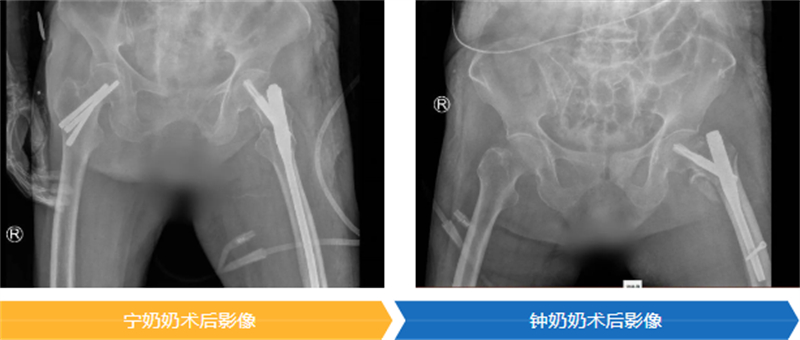

手術是讓老人重獲生機的關鍵一步,但同時也是對百歲高齡軀體的嚴峻挑戰。為了以最小的創傷換取最大的生存機會,醫療團隊為兩位老人精心選擇了“股骨近端防旋髓內釘(PFNA)”這一微創固定方案。

時間就是生命。在醫院為高齡患者開通的綠色通道保障下,兩位老人均在入院24小時內接受了這關鍵性手術,并順利完成。隨后,在重癥監護室(ICU)團隊的晝夜精心守護下,兩位百歲老人平穩渡過了術后最危險的階段,為后續的康復贏得了寶貴的時機。

在大家溫暖的鼓勵和專業的幫助下,寧奶奶在手術后第三天,就穩穩地站起來了;鐘奶奶也在第五天,堅強地扶著助行器邁開了步子。能早點下床,就意味著能把肺炎、血栓這些“臥床病”遠遠推開,恢復得更順利,也能早一點回家。